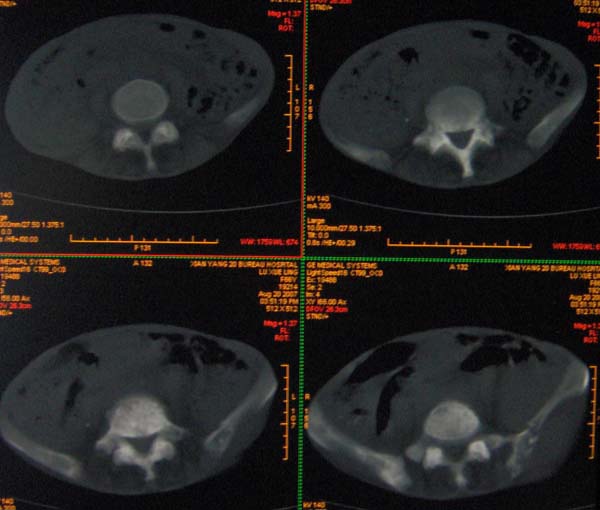

以下是引用ybing在2007-8-22 20:31:00的发言:[br]左侧髂骨溶骨样破坏;软组织肿块形成;其内未见肿瘤骨考虑纤维肉瘤或滑膜肉瘤不除外转移瘤

以下是引用qiushi在2007-8-22 21:39:00的发言:[br]双侧髂骨、骶骨侧快呈溶骨样骨质破坏,边缘模糊,左侧髂骨见骨折线,左侧髂部见软组织块影。考虑骨纤维肉瘤(中央型)伴病理性骨折,不排除骨髓瘤。建议本--周氏蛋白检查。[br] 鉴别点:[br] 骨纤维肉瘤,中央型者示边缘模糊的囊状溶骨破坏,一般无骨膜反映,可膨胀变形,突破骨皮质可形成软组织肿块,或并发病理性骨折。[br] 骨髓瘤,常表现为广泛的骨质疏松,皮质变薄或破坏,呈粟栗状、穿凿状、鼠咬状骨质破坏,边缘清晰,周围无硬化。[br] 骨转移瘤(溶骨型),表现为虫噬样、泡沫状圆形或卵圆形破坏区,很少出现软组织块影。[br][br][本贴已被 qiushi 于 2007-8-23 6:20:19 修改过]